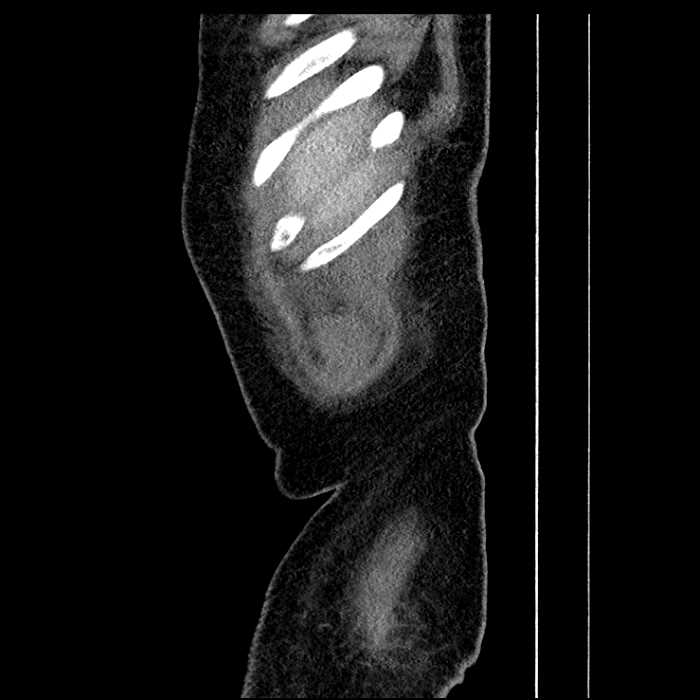

• Lower chest

• Mild cardiomegaly

• Mild dependent atelectasis

• Large fluid density structure in hepatic segments 7 and 8 measuring 10 x 7 x 7 cm with internal septation and circumferential ill-defined low density compatible with edema

• Peripherally enhancing subcapsular collections along the anterior margin of the left hepatic lobe measuring 3 x 1 cm and 2 x 1 cm

• Clearly marginated fluid density structure in segment 7 and several other scattered tiny hypodensities, which likely represent cysts

Hepatic abscess showing the double target sign with low density internally surrounded by a thin inner enhancing rim (red arrow) and ill-defined outer low density rim (yellow arrow). Blue arrow indicates an internal septation. Red arrows: additional smaller subcapsular abscesses. Red arrow: focal contained perforation associated with diverticulitis.